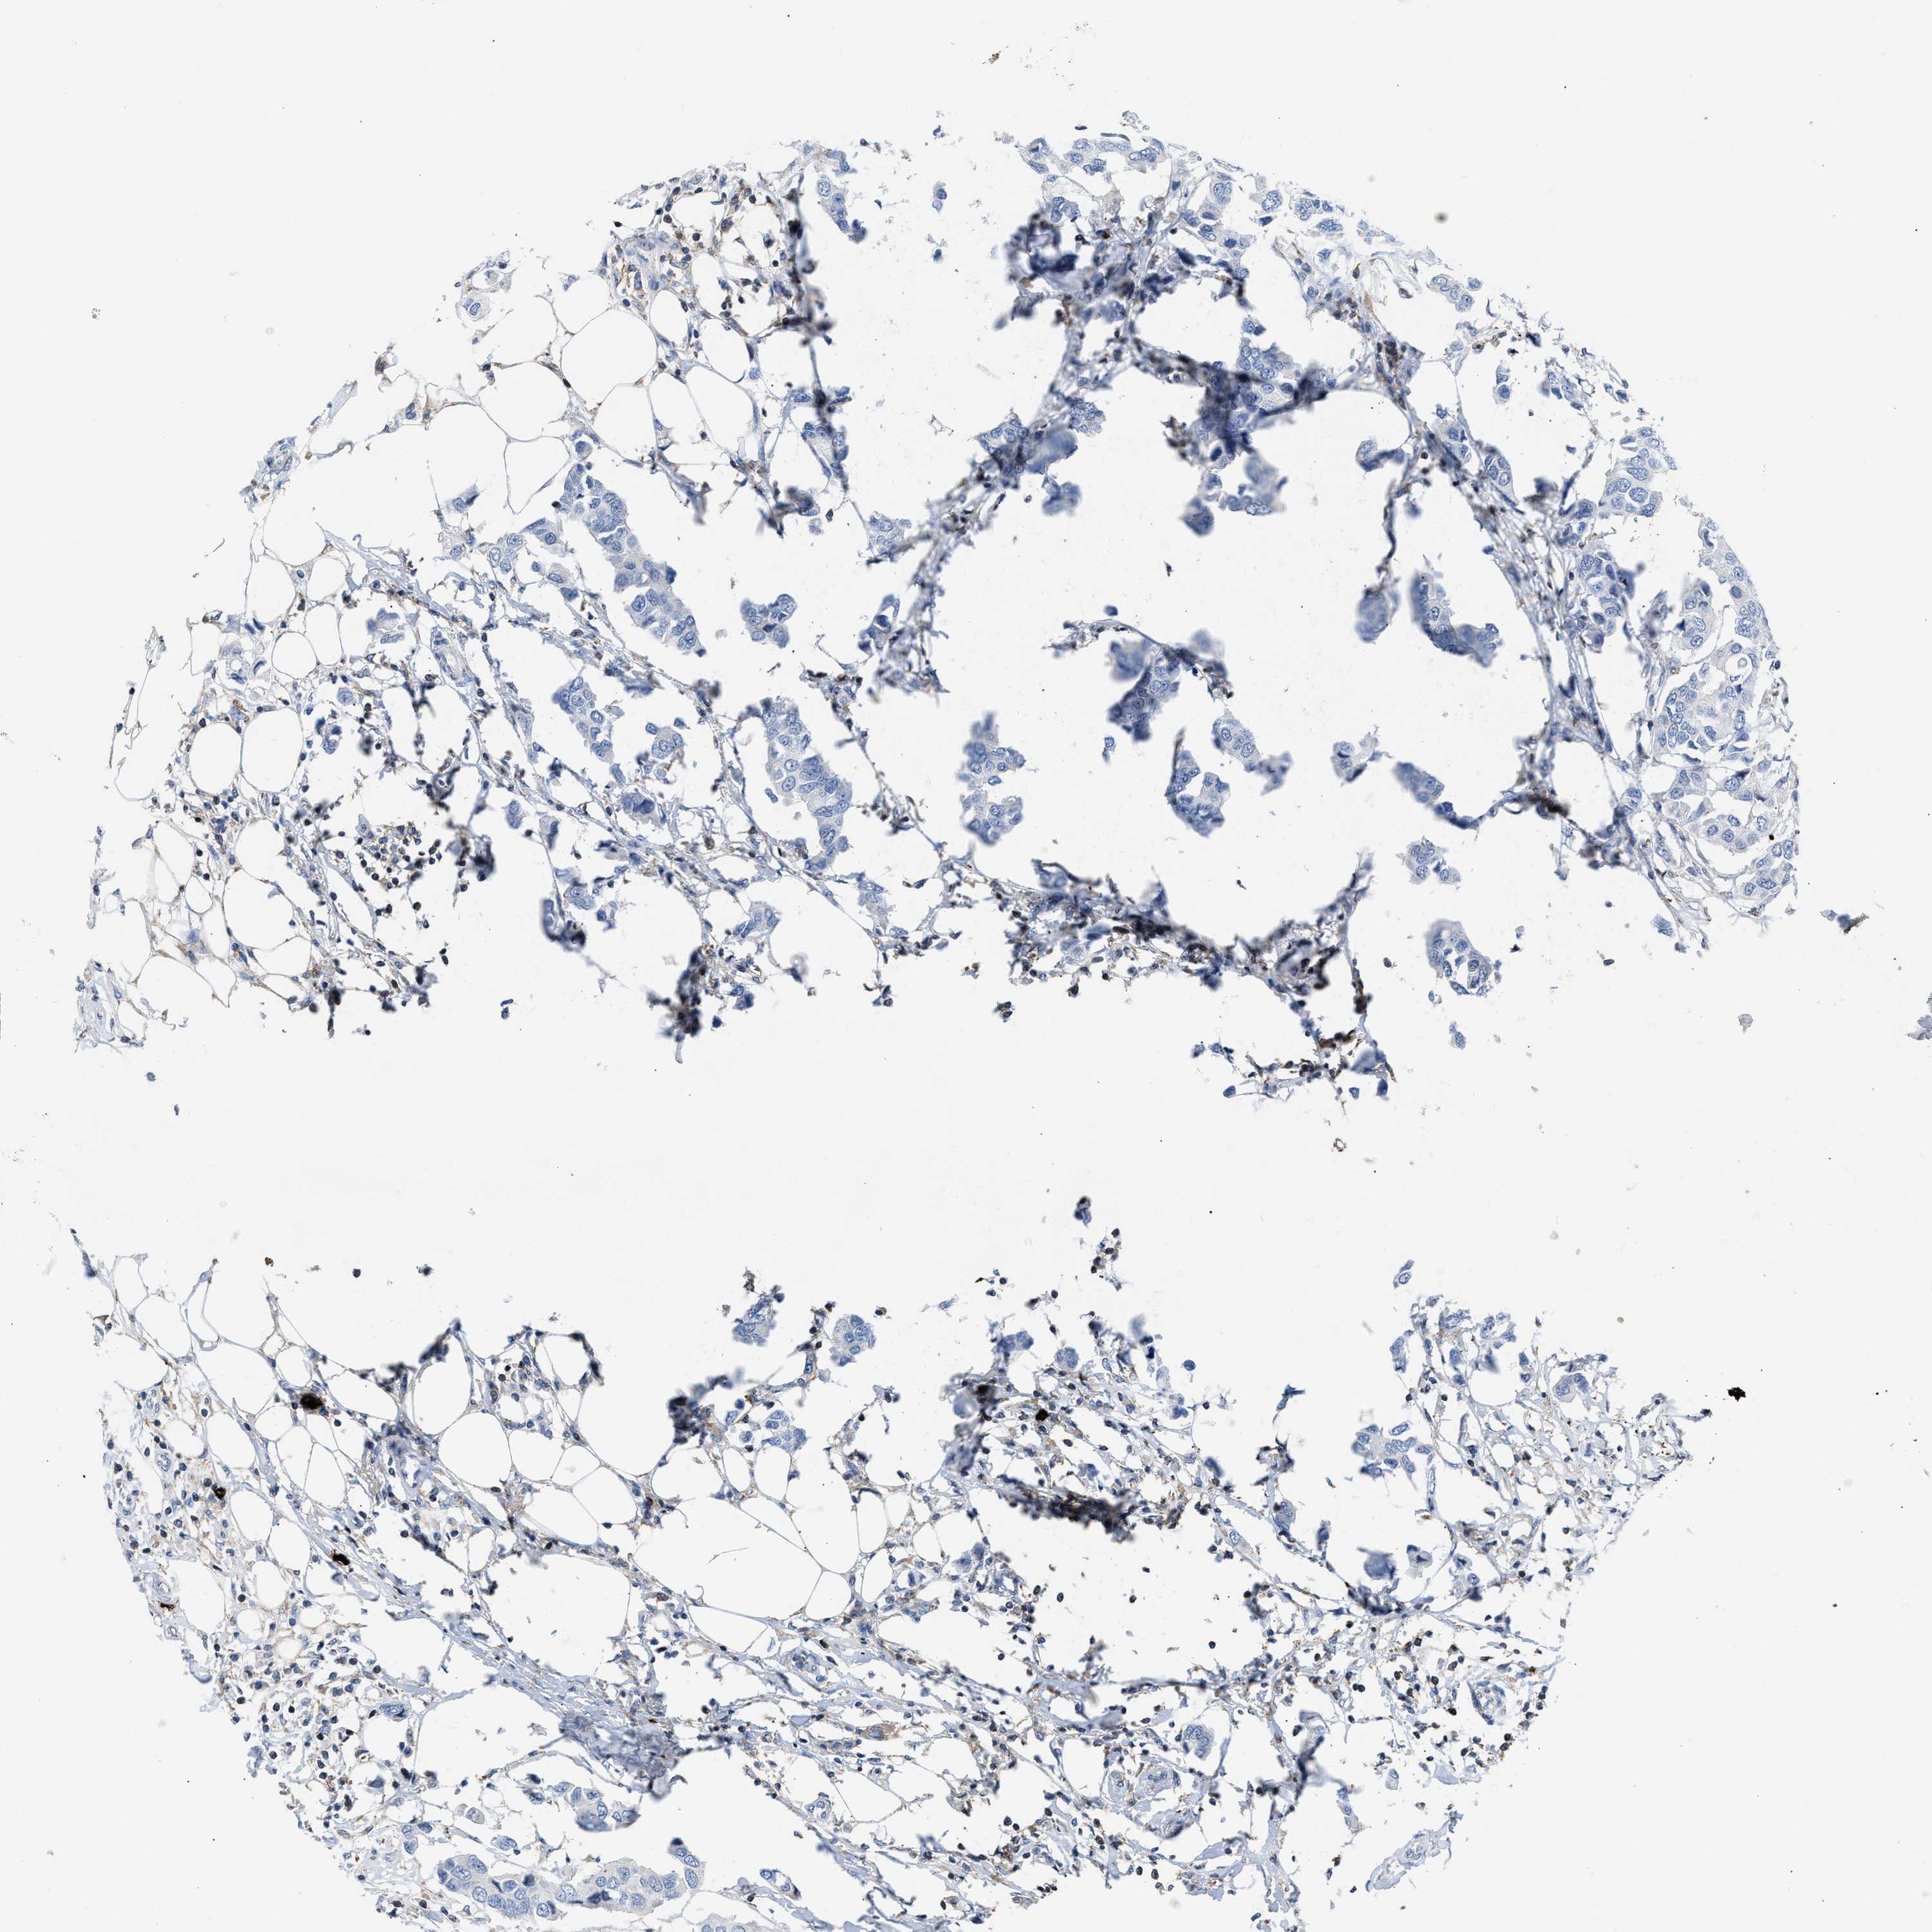

CANCER BREAST CANCER Show tissue menu

BRCA TCGA BRCA VALIDATION PROTEIN EXPRESSION

Breast cancer

Human cancer